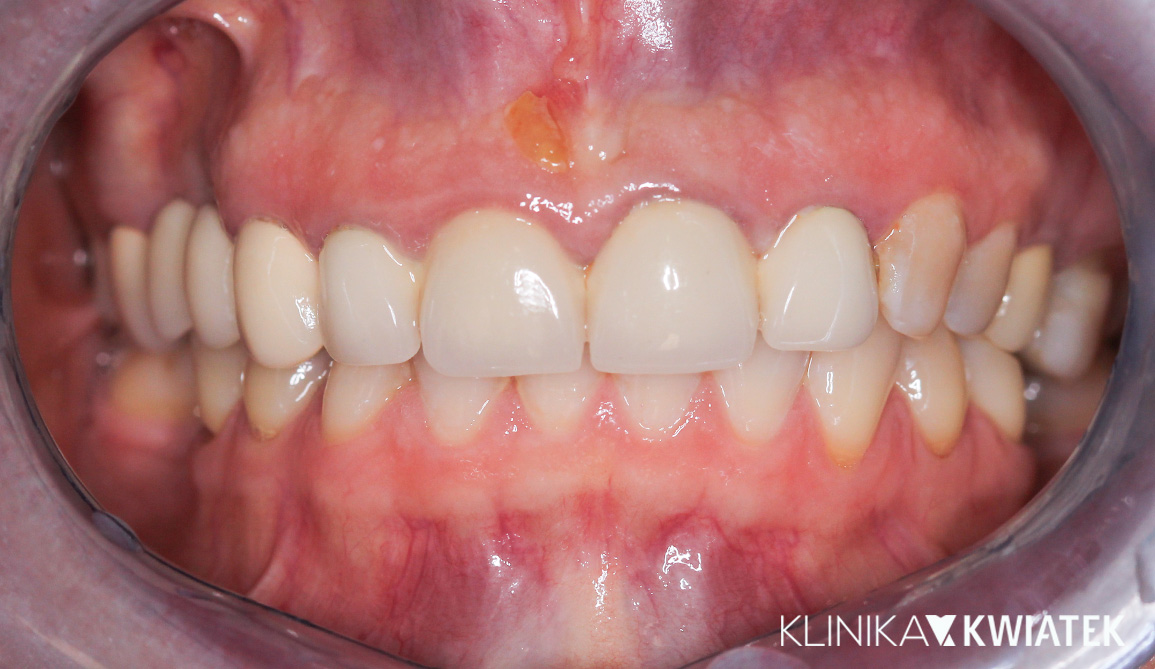

PO

Uśmiech, który zmienia wszystko – kompleksowa metamorfoza dzięki korekcie wady zgryzu i estetycznej przebudowie

Pacjentka zgłosiła się z powodu napięć mięśniowych, zgrzytania zębami i dolegliwości ze strony stawów skroniowo-żuchwowych. Rozpoczęto terapię od szyny relaksacyjnej i fizjoterapii, a następnie wdrożono leczenie ortodontyczne oraz kompleksową odbudowę protetyczno-estetyczną. Efekt końcowy to nie tylko zdrowy zgryz i brak dolegliwości bólowych, ale także piękny, naturalny uśmiech.